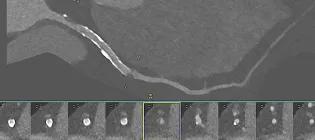

Ultra-high-resolution photon-counting CT imaging of a coronary artery in a patient with coronary artery disease and a previous stent.

Senior Research Fellow

I research heart attacks using routine data and advanced imaging techniques to improve diagnosis and treatment for patients.

A.R.Chapman@ed.ac.uk